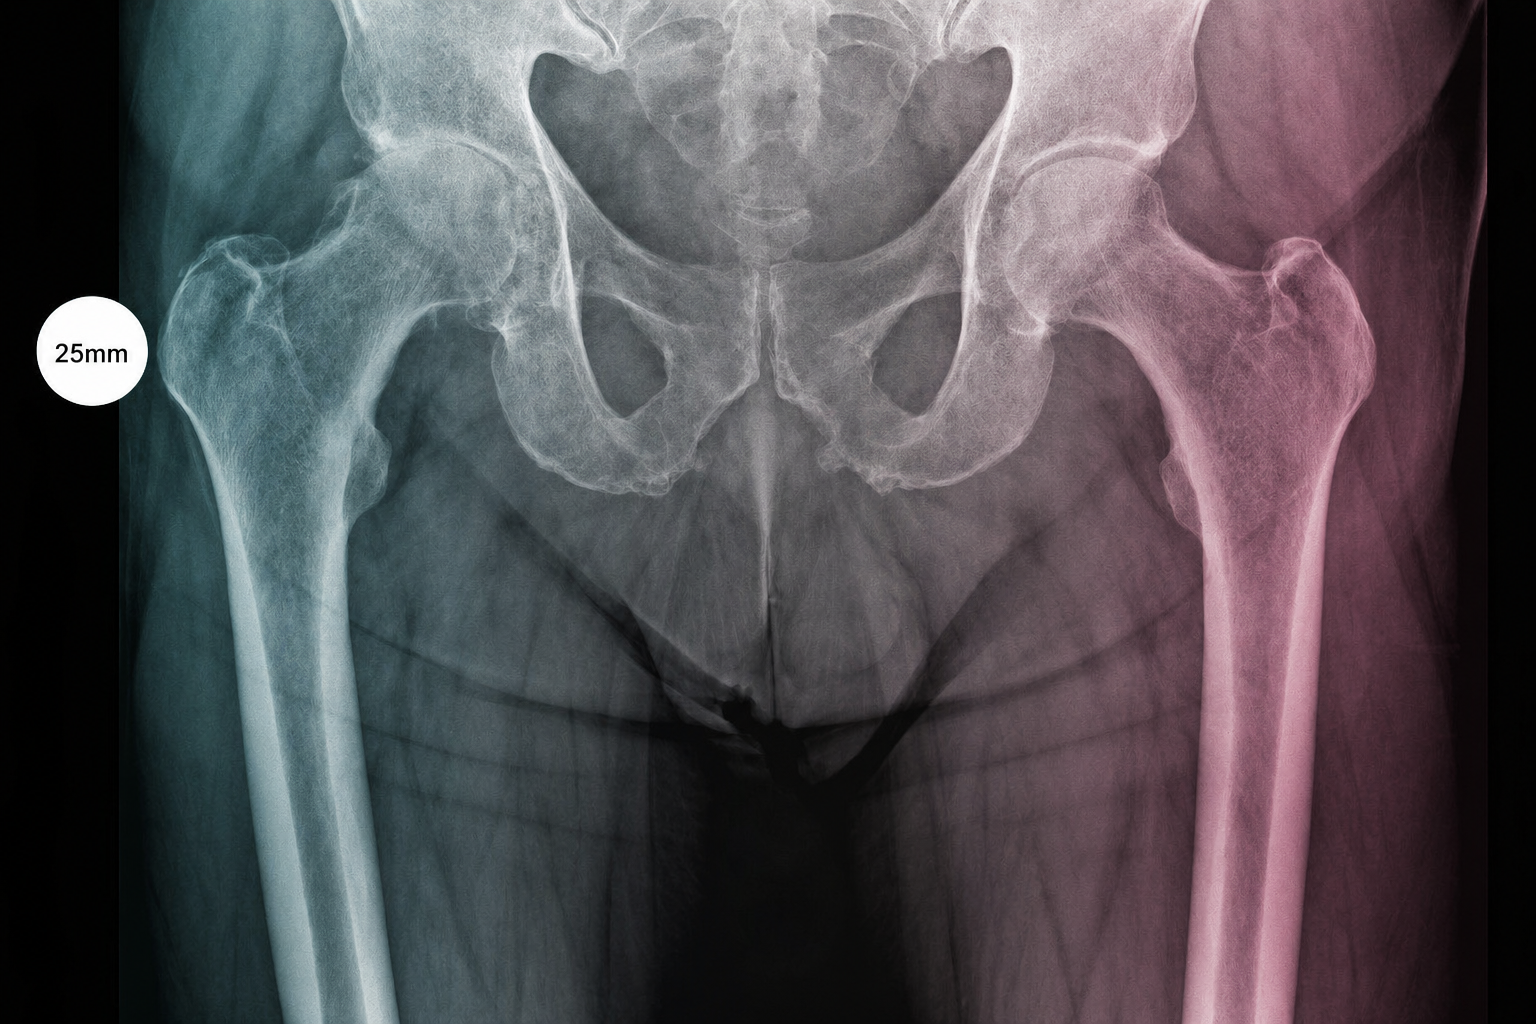

A compact guide for radiology teams on correct calibration sphere placement in orthopedic X-ray imaging. The marker must be positioned in the anatomical plane of the target joint so that digital scaling, measurements and preoperative templating remain clinically reliable.